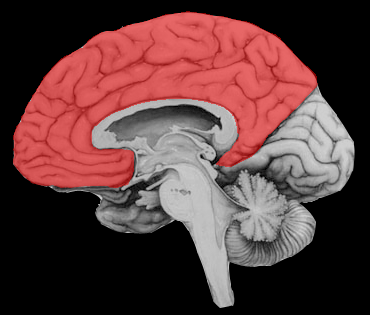

Territoire de l’artère cérébrale antérieure